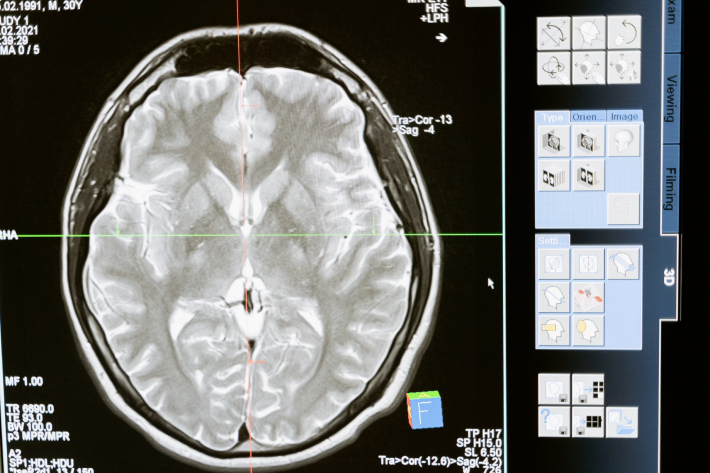

El sistema utiliza un pequeño transmisor que pesa poco más de 40 gramos. En vez de cables, se coloca una unidad sobre la cabeza del usuario, se conecta con una matriz de electrodos en la corteza motora de cerebro y utiliza el mismo puerto que emplean los sistemas de cable.